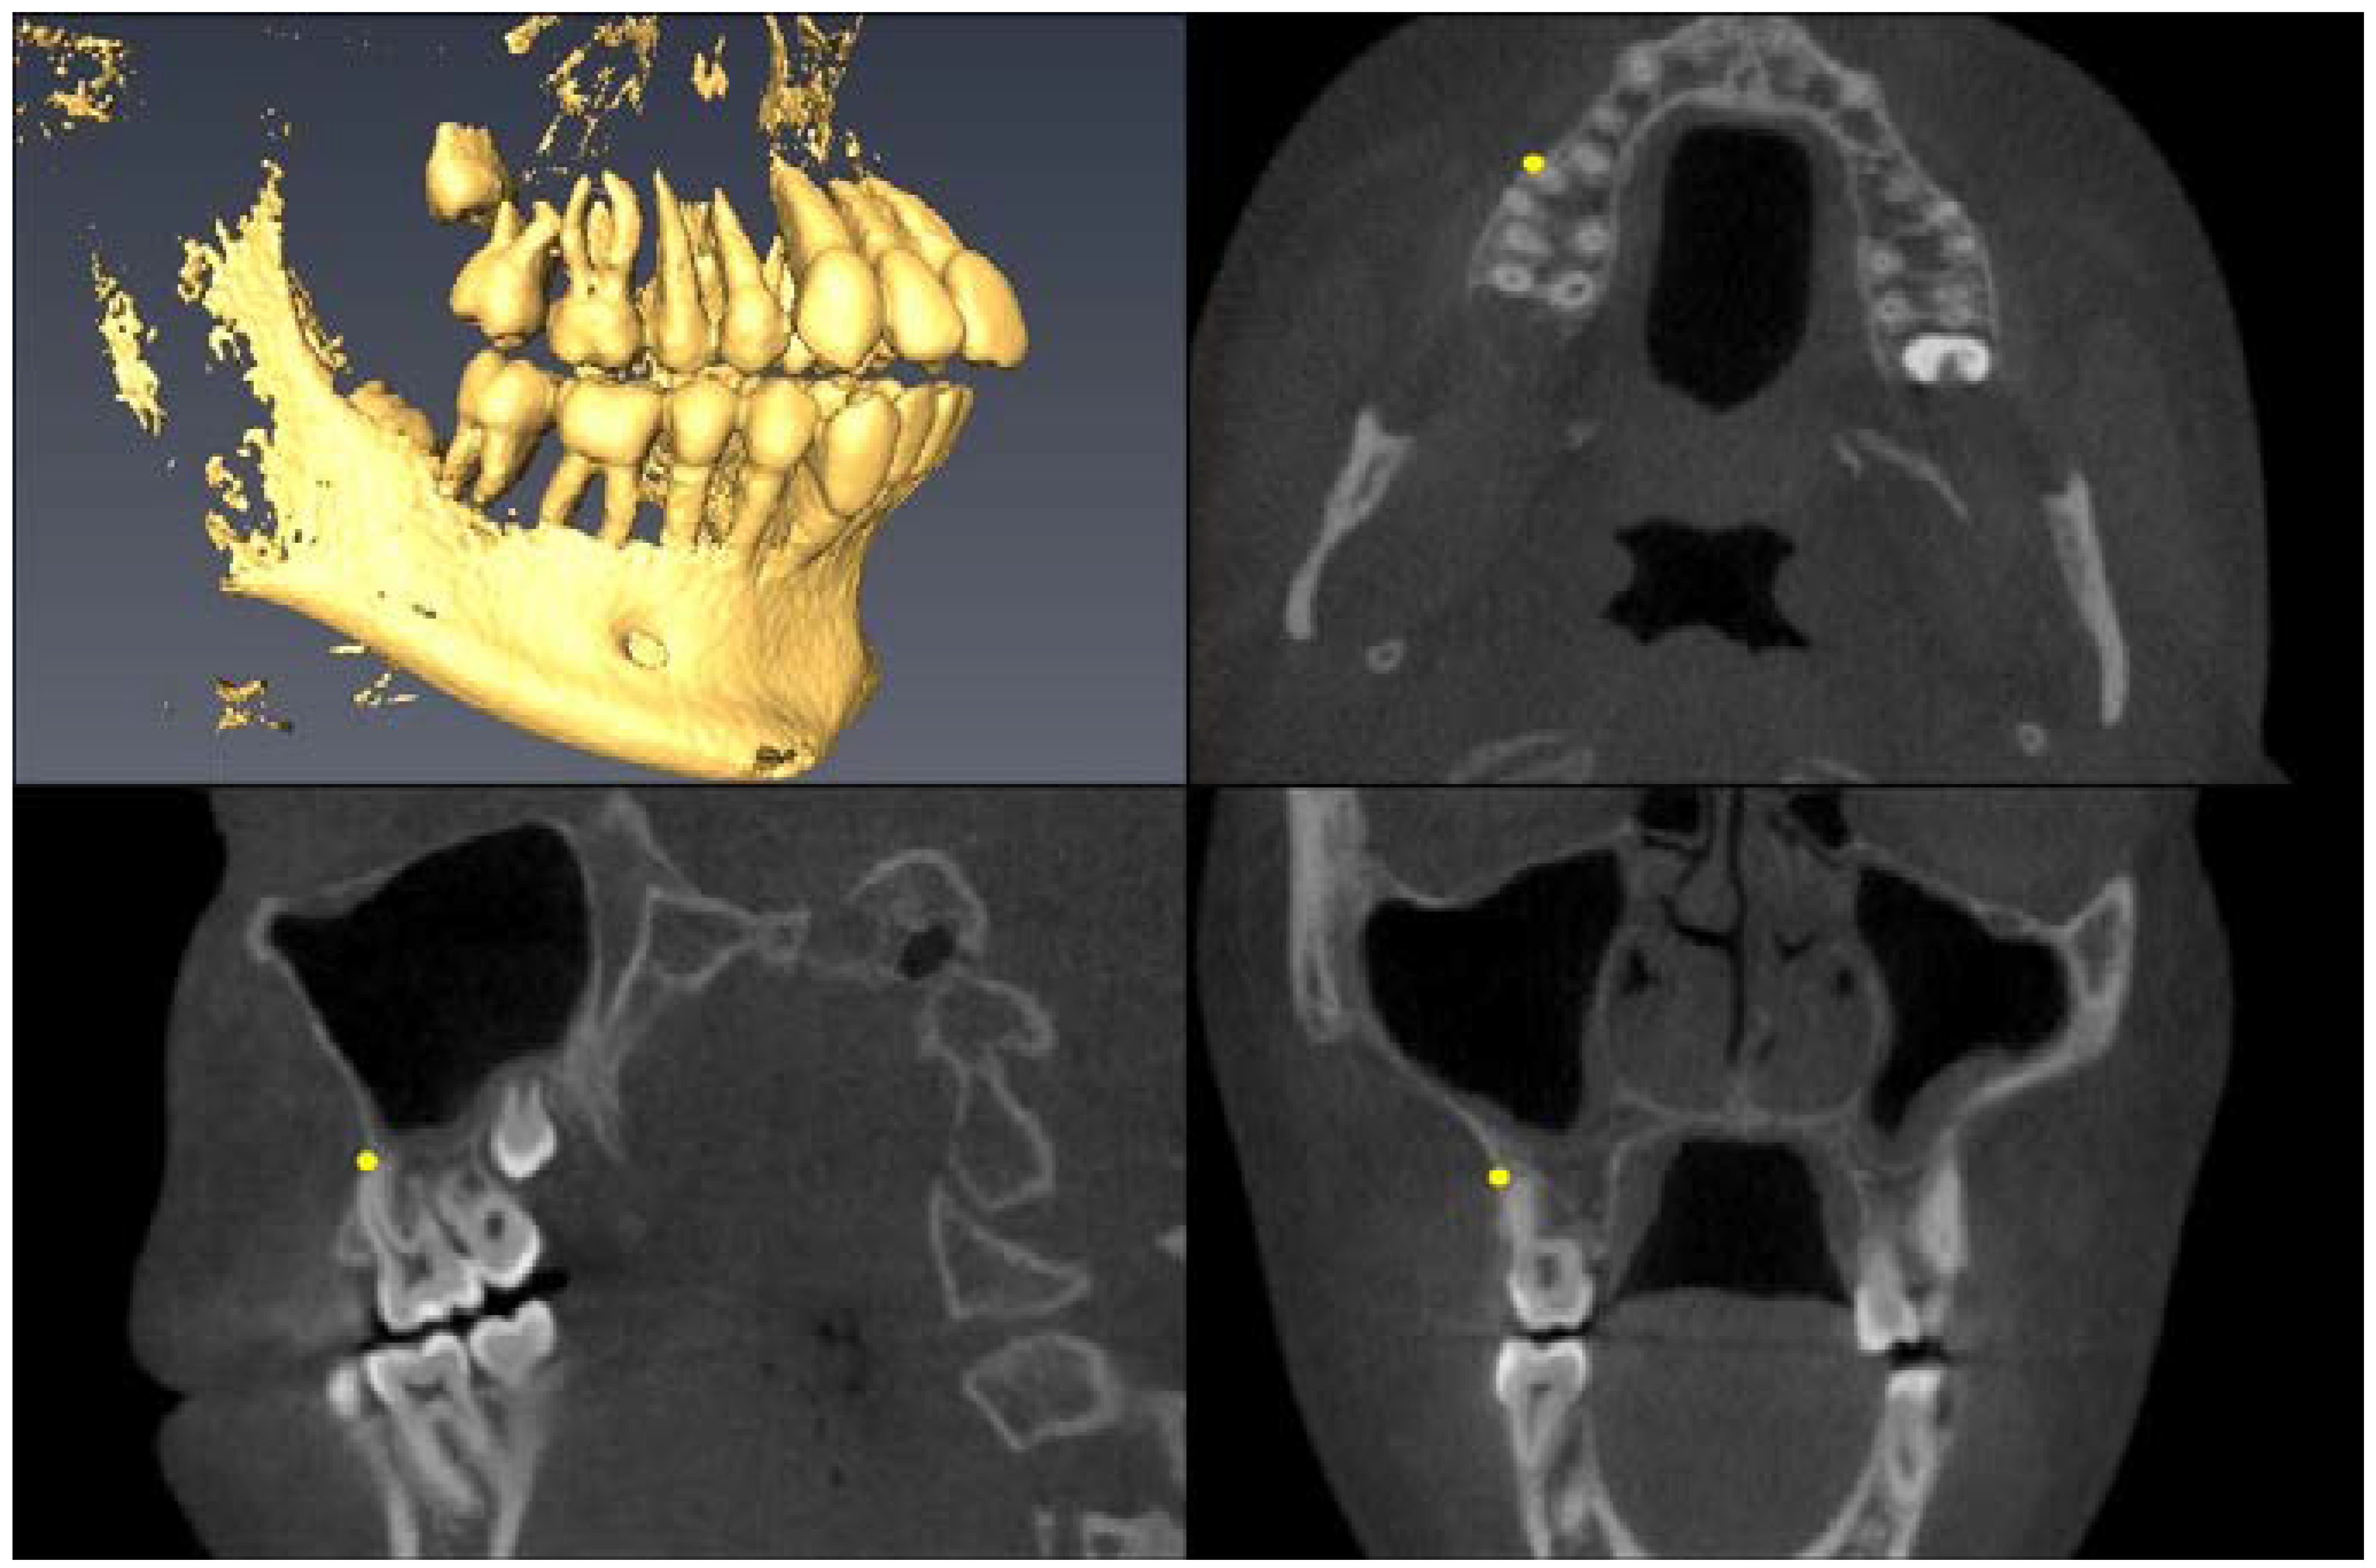

| Landmark Description | 3D View (Upper Left), Axial View (Upper Right), Sagittal View (Lower Left), Coronal View (Lower Right) |

| Upper First Molar Mesial Root Apex =apex of mesio-buccal root | ![]() |